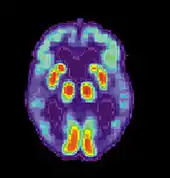

PET scan of a healthy brain - Image courtesy of US National Institute on Aging Alzheimer's Disease Education and Referral Center

PET scan of brain with AD - Image courtesy of US National Institute on Aging Alzheimer's Disease Education and Referral Center